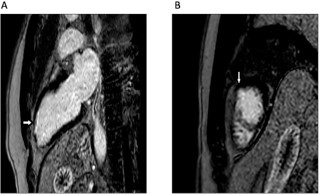

Cardiac Magnetic Resonance imaging (CMR) was obtained for functional assessment. Resting images demonstrated a subendocardial defect in the LAD territory, while late gadolinium enhancement confirmed infarction (Figures 3A & 3B). Left ventricular systolic function was preserved (ejection fraction 58%). CMR is particularly valuable in confirming ischemia and tissue injury in MB-related ACS [4,15].

Figure 3: Cardiac Magnetic Resonance imaging (CMR) demonstrating evidence of infarction. (A) Still image of CMR left 2 chamber view showing late gadolinium enhancement in mid LAD territory, indicating infarction (white arrow); (B) Still image of CMR short axis view showing late gadolinium enhancement in mid LAD territory, indicating infarction (white arrow).